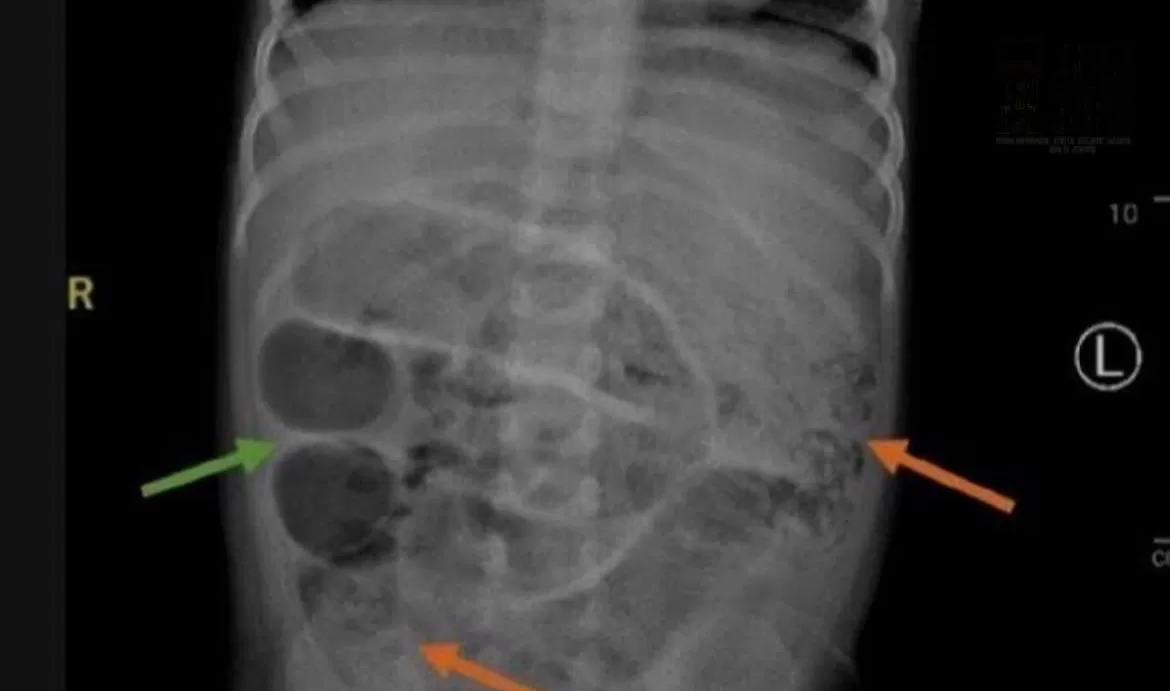

Hasil Rontgen Anak yang di Perutnya Terdapat Cacing Pita. (instagram.com/jemberinfo_)

JEMBER, suararembang.com - Kasus mengejutkan terjadi di Jember, Jawa Timur. Seorang anak berusia tiga tahun harus menjalani perawatan medis setelah ditemukan cacing pita sebanyak tiga toples memenuhi ususnya.

Cacing yang ditemukan tergolong jenis ascaris atau ascariasis, yaitu parasit yang umum dijumpai di daerah tropis, terutama wilayah dengan sanitasi buruk seperti beberapa bagian di Jember dan Bali.

“Cacing ini berasal dari tanah. Jika tertelan, bisa hidup dan berkembang biak di usus atau lambung,” jelas dr. Bela.